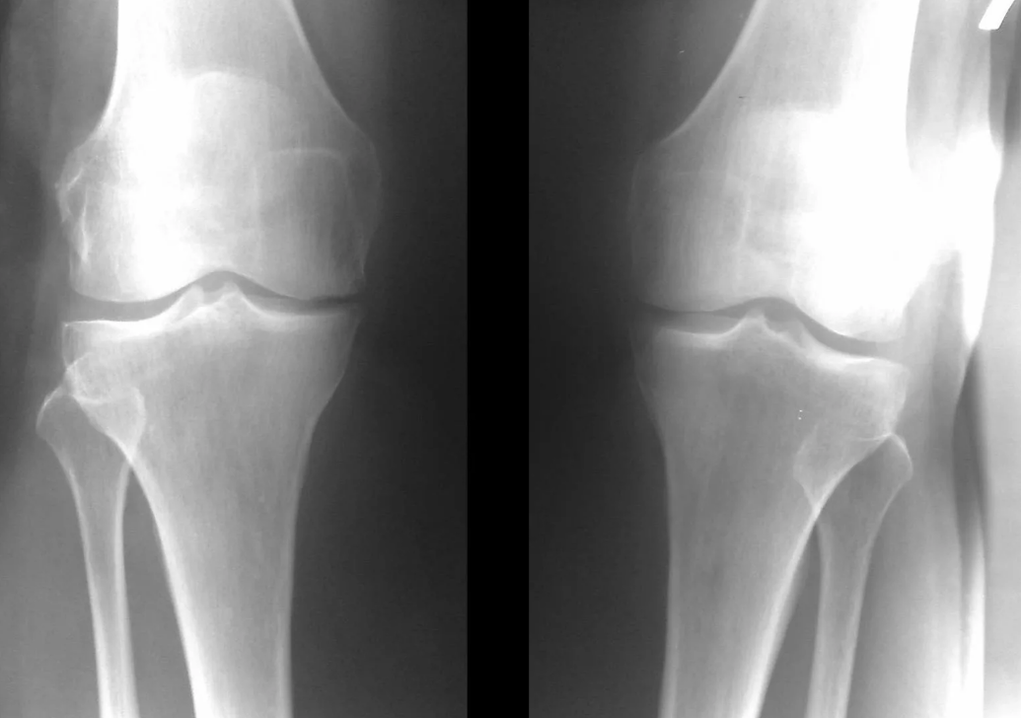

In most cases, examination and radiography of the knee joint in two projections (direct and lateral) are sufficient.Clinical data and images help determine the stage of the disease.

diagnosis of arthrosis of the knee joint

In the early stages of the disease, with small changes in bone tissue, X-ray examination is not so valuable.At this stage, gonarthrosis can be diagnosed through arthroscopy.The accuracy of the method is very high;only its invasive nature and cost can stop it.

Ultrasound does not allow clear visualization of changes in articular cartilage and intra-articular structures.Using MRI, you can detect changes in the bone, cartilage and soft tissue structures of the joint, as well as in the subchondral bone, with 85% accuracy.Scintigraphy can be used to evaluate the metabolic activity of periarticular bone tissue.